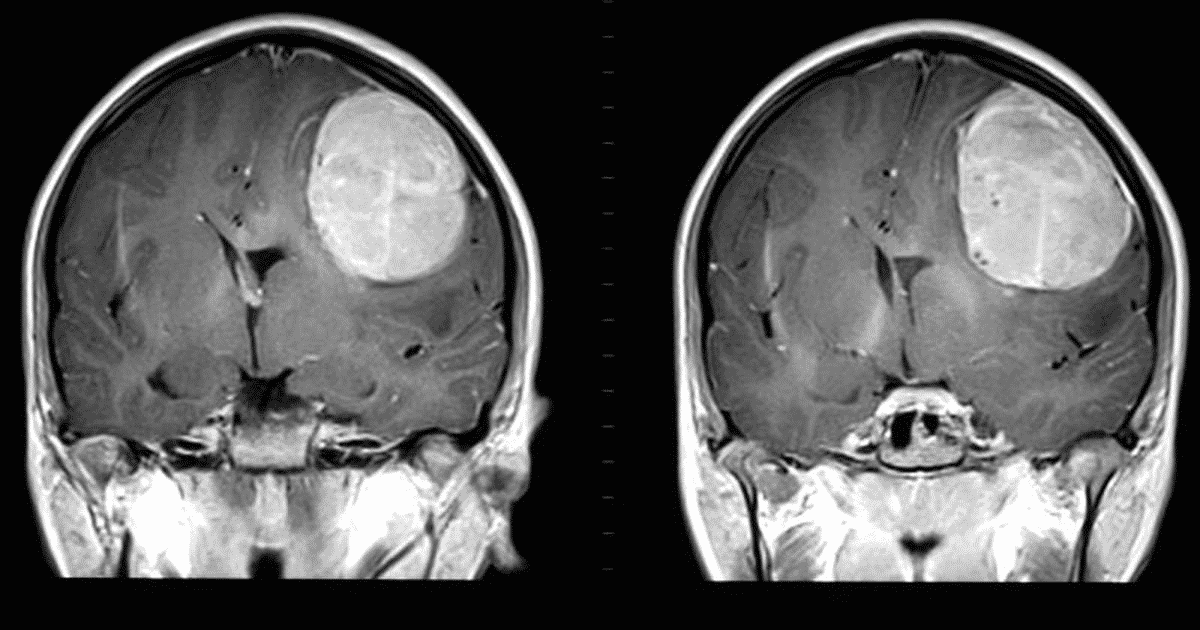

“Electric Cap” Shown to Prolong Survival in Deadly Brain Cancer

For patients diagnosed with glioblastoma, an aggressive form of brain cancer that strikes about 3 in 100,000 patients in North America each year, the prognosis is bleak. Only five per cent of patients live past five years, and no study in the last decade has found a way to improve survival rates. Earlier this year, Tragically Hip frontman Gord Downie died after a high-profile battle with glioblastoma, and Republican U.S. Senator John McCain continues to fight the disease.